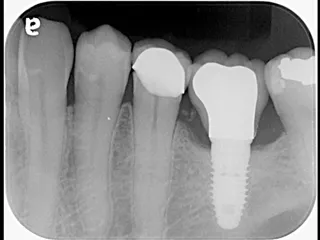

CASE No.3 奈良 嘉峰 先生(神奈川県茅ヶ崎市開業)

Labrida 施 術 前

施 術 前 (レントゲン写真)

Labrida  施 術 後(4週後 )

炎症とBOP消失